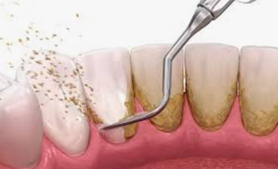

歯石が多く沈着し歯周病が進行している状態

歯の磨き残しによりできた、口腔内のプラーク(細菌の塊)および歯石(プラークが石灰化したもの)を除去し、お口の中の清掃状態を良好に維持することが歯周病の治療になります。

実際の治療としては、まず歯面のプラークおよび歯石の付着状況・歯周ポケットの深さ・歯肉からの出血の有無・歯の動揺度を検査、測定し、歯肉炎および歯周炎に罹患しているかどうかを確認します。

検査にて歯肉炎・歯周炎と診断された場合は、スケーラーと呼ばれる専門の器具を用いて、プラークおよび歯石除去を行います。状態によっては痛みを伴う場合がありますので、必要に応じて麻酔を行う場合があります。